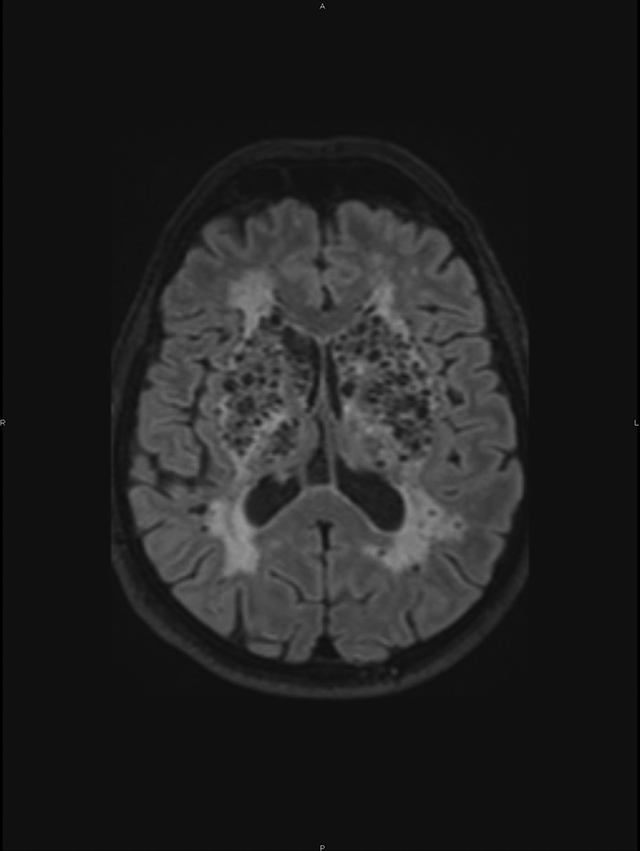

A conglomerate of multiple, symmetric, well-circumscribed round/oval lesions. These lesions presented high signal in T2-weighted sequence (Figure 1) and low signal in T1 (Figure 2) and in T2 fluid-attenuated inversion recovery (Figure 3). No diffusion abnormalities were identified. No enhancement was detected after contrast media administration.

Figure 2

Low signal in T1.